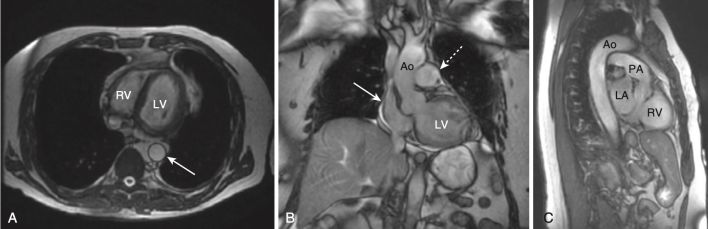

Giải phẫu MRI tim bình thường

- Một trong những lợi ích của MRI là hình ảnh của nó có thể được hiển thị ở bất kỳ mặt phẳng nào. Bên cạnh các mặt phẳng cắt ngang (axial), đứng dọc (sagittal) và đứng bên (coronal, trán), có một số góc nhìn đặc hiệu thường được sử dụng trong MRI tim cho phép hình dung rõ nhất về tim. Chúng được gọi là trục dài cắt ngang (còn được gọi là mặt cắt bốn buồng), trục dài thẳng đứng, trục ngắn và mặt cắt ba buồng.

- Cấu trúc giải phẫu của tim trong các mặt phẳng cắt ngang, đứng dọc và trán giống như được thấy trên CT (Hình 16).

- Mặt cắt trục dài cắt ngang (bốn buồng) giống hình cắt ngang và được sử dụng tốt nhất để đánh giá vách ngăn và thành bên và đỉnh của tâm thất trái, thành tự do của tâm thất phải và kích thước của các buồng tim. Các van hai lá và van ba lá đặc biệt nhìn rõ ràng trong hình ảnh này (Hình 17).

- Trục dài đứng dọc giống như lát cắt đứng dọc và được sử dụng để đánh giá thành trước và thành dưới và đỉnh của tâm thất trái (Hình 18).

- Lát cắt trục ngắn mô tả tâm thất trái và phải để thực hiện các đo lường thể tích (Hình 19).

- Bởi vì hình ảnh MRI của tim đã được thu được với các thể tích ba chiều ở cả cuối tâm thu và cuối tâm trương, có thể thực hiện các đo lường khối lượng tâm thất, thể tích cuối tâm trương và thể tích cuối tâm thu dựa trên máy tính, và qua đó tính được thể tích nhát bóp và phân suất tống máu mà không cần can thiệp.

- Lát cắt ba buồng tương tự như lát cắt đứng bên và hiển thị gốc động mạch chủ và van động mạch chủ, đường ra thất trái, van hai lá, các thành trước vách và thành dưới bên của tâm thất trái (Hình 20).

- Tùy thuộc vào chuỗi xung MRI được sử dụng để thu được hình ảnh, máu có thể được mô tả là đen (thường sử dụng một xung gọi là chuỗi xung spin echo) và thường được sử dụng để đánh giá giải phẫu, hoặc sáng, nghĩa là màu trắng (thường sử dụng một chuỗi xung gọi là chuỗi xung echo gradient), và thường được sử dụng nhất để đánh giá chức năng (Hình 21).